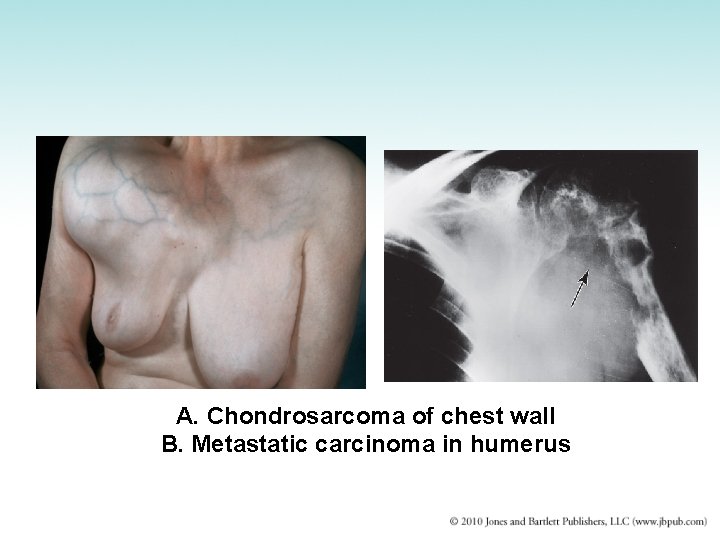

Tumors of the Bone • Usually metastatic tumors from prostate, breasts, other organs • Multiple myeloma: plasma cell neoplasm • Benign cysts and tumors: encountered occasionally • Primary malignant bone tumors: unusual – Chondrosarcoma: malignant tumor of cartilage – Osteosarcoma: malignant tumor of bone-forming cells

A. Chondrosarcoma of chest wall B. Metastatic carcinoma in humerus